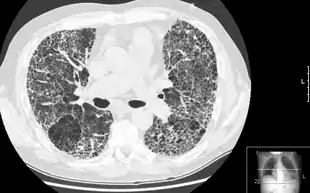

HRCT of lung showing extensive fibrosis possibly from usual interstitial pneumonitis. There is also a large emphysematous bulla. | |

HRCT is used for diagnosis and assessment of interstitial lung disease, such as pulmonary fibrosis, and other generalized lung diseases such as emphysema and bronchiectasis.

HRCT may be diagnostic for conditions such as emphysema or bronchiectasis. While HRCT may be able to identify pulmonary fibrosis, it may not always be able to further categorize the fibrosis to a specific pathological type (e.g., non-specific interstitial pneumonitis or desquamative interstitial pneumonitis). The major exception is UIP, which has very characteristic features, and may be confidently diagnosed on HRCT alone.[9]